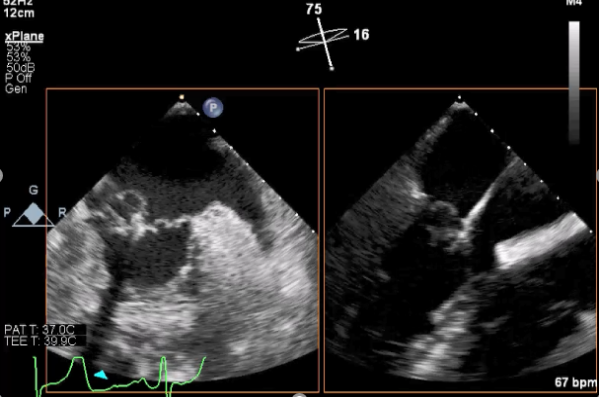

三维超声心动图显示第一枚XTR夹子释放,残余返流主要位于外侧

引导第二枚XTR夹子转向外侧残余病变区域并逐渐进入左室

第二枚XTR夹子释放,返流明显减少

三维超声心动图显示第二枚XTR夹子释放